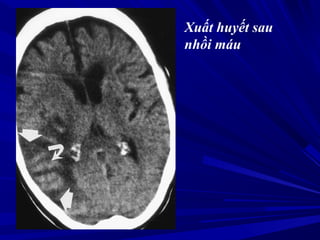

Xuất huyết sau

nhồi máu

Nhồi máu não cũ